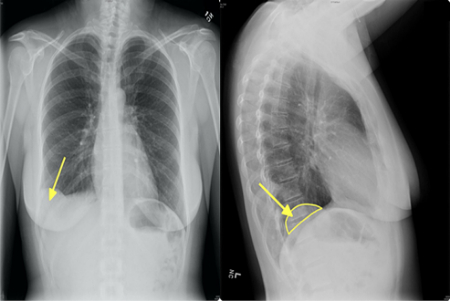

تشخیص

هامارتوماها اغلب به طور اتفاقی در تصویربرداری برای مشکل دیگری کشف میشوند. برای تأیید تشخیص ممکن است نیاز به آزمایشهای تصویربرداری زیر باشد:

• سیتی اسکن (CT scan)

• امآرآی (MRI)

• رادیوگرافی (اشعه ایکس)

در صورت شک به سرطان، ممکن است بیوپسی (نمونهبرداری) انجام شود.

۳٫ هامارتومای ریه چقدر شایع است؟

شایعترین هامارتومای خوشخیم ریه است (حدود ۷۰–۸۰٪ تومورهای خوشخیم ریه).

بیشتر در بزرگسالان ۴۰–۶۰ سال دیده میشود و در مردان شایعتر است.

۴٫ آیا هامارتومای ریه باید عمل شود؟

اگر کوچک باشد و علامتی نداشته باشد → معمولاً فقط پیگیری با سیتی اسکن هر ۶–۱۲ ماه. اگر بزرگتر از ۲.۵ سانتیمتر باشد، در حال تومور باشد یا علائم (سرفه، تنگی نفس) بدهد → جراحی (معمولاً با VATS یا جراحی کمتهاجمی).